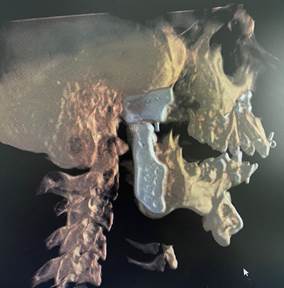

The second step is conversion of the imaging data into three dimensional digital models of the face.

Once the 3D reconstructed models are obtained, the surgeon and the engineers simulate the surgical steps on the model. The ankylotic mass is removed and the prosthetic components are positioned digitally in the desired position replicating normal anatomy.

Based on the virtual surgical planning, the patient-specific implants are customised. Along with these implants, surgical guides are fabricated to aid in surgical precision and improved surgical time.

The post-operative CT scan showing the temporomandibular joints on both sides and the titanium miniplates used for fixation of the upper and lower jaw after bijaw orthognathic surgery.